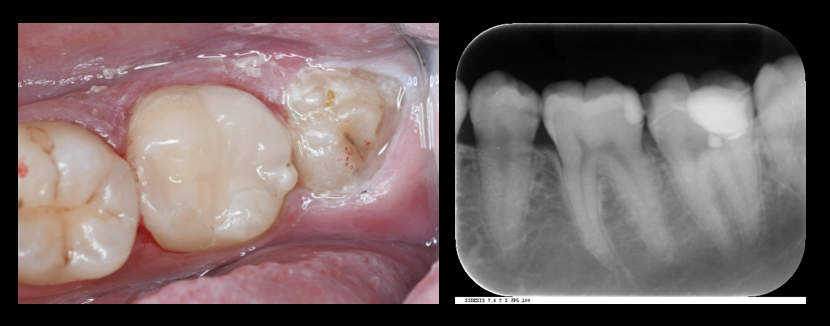

写真左:術後の口腔内:レジンセメント:パナビアV5クリア にてセット

写真右:術後のレントゲン写真

ここまで全て即日でおこなっております(治療1回)

神経(歯髄)の保存のチェックを経過みて行なっていきます。